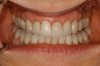

Figure 15 – Extraction of anterior tooth No. 8 without detaching the gingiva.

Figure 15

Figure 16 – Extracted tooth with the root canal material (gutta percha) extending from the apex

Figure 16

Figure 17– A zircon (white) abutment was attached immediately after extraction and implant placement.

Figure 17

Figure 18 – Immediate placement of temporary crown over the abutment; laser crown lengthening was performed on the adjacent teeth to improve gingival symmetry

Figure 18

Figure 19 – Four months after surgery with temporary crown over the implant at No. 8.

Figure 19

A dental implant most closely replicates natural tooth structure. Once it is osseointegrated, many patients cannot differentiate an implant from a natural tooth. Furthermore, dental implants do not decay or need root canal therapy. Even though the cost is slightly more than a bridge, it is an investment for the future, as implants usually last longer than a bridge. A 10-year report on posterior single implants shows a success rate of 97%.33 Once an implant is placed, the osseointegration and tissue healing time of approximately 4 months is necessary before a final crown is placed. A temporary crown can be placed the same day the implant is placed, but this is only for esthetics, not for function (Figure 15 through Figure 19).